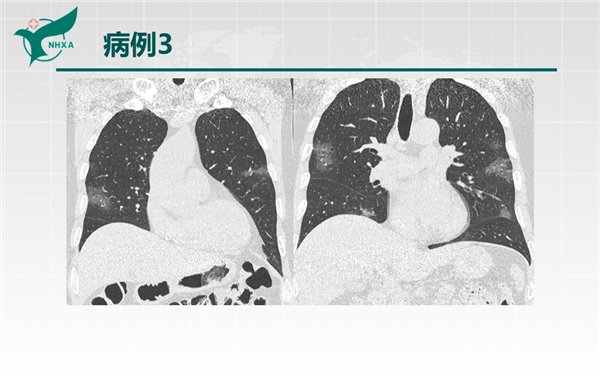

【病例分享】新型冠狀病毒肺炎3例(西安市第九醫(yī)院)

幻燈片6.jpg